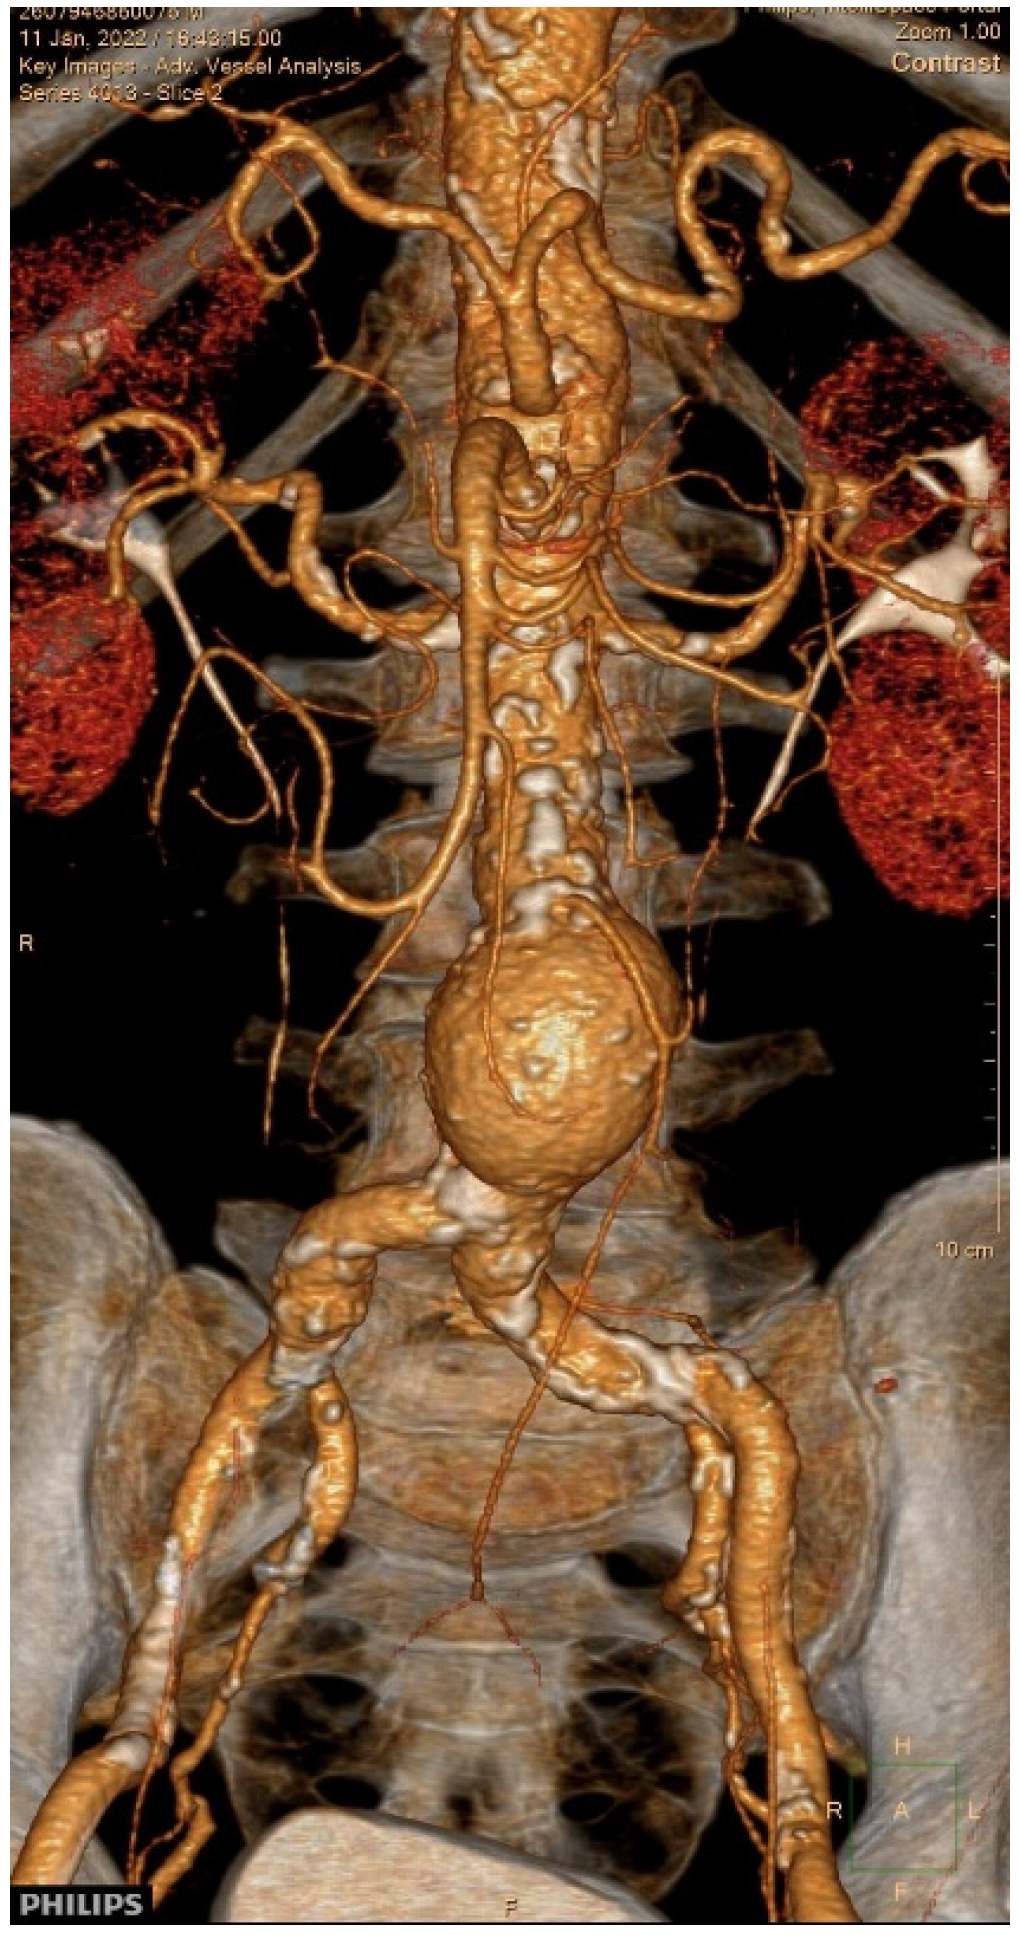

2. Case Presentation

3.8. Our Case